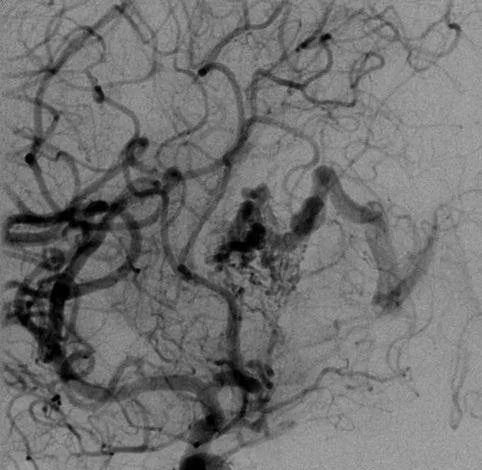

▼该AVM由ACA/PcaA分支、ACoA穿支和mPChA供血[右侧ICA造影

▼(a)侧位s(b)前斜位